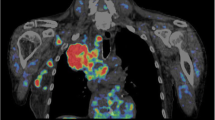

Five of the 22 patients had synchronous liver metastases of their primary colorectal tumour at the time of the PET examination. The metastases were confirmed by surgery and histology. To assess whether differences existed in the metabolism of the primary tumours, we performed a subgroup analysis of the PET parameters of the primary tumours, comparing patients with only a primary colorectal tumour to those with synchronous liver metastases (Table 4). There was a trend towards lower V B values and k 1and k 2 seemed to be higher in patients with tumours and metastases, but no statistically significant difference was achieved for the individual parameters when p < 0.01 was used. Furthermore, all other parameters, including SUV, appeared to be lower in the group with tumours and metastases, but no significance level was achieved with the single parameter analysis. The SVM analysis using FSCORE feature elimination and polynomial hyperplane generation combined the PET parameters and provided a correct identification of three of five patients with metastases, based on V B, k 1 and k 2 of the primary tumours (Fig. 4).

Probability map for patients with colorectal tumours (blue, n = 17) and patients with colorectal tumours and synchronous liver metastases (red, n = 5). The SVM algorithm was applied to the PET data of the primary tumours and provided a correct prediction of metastases in three of five patients with surgically and histologically confirmed metastatic lesions